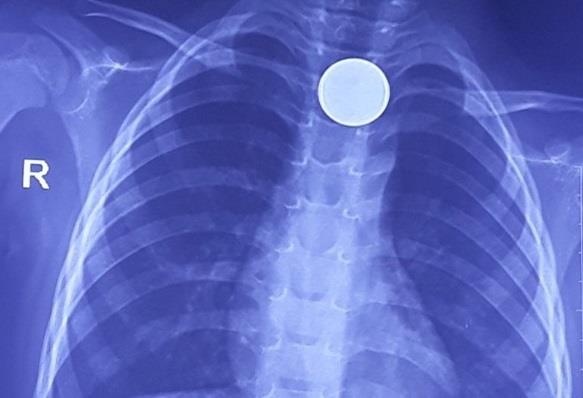

Hình ảnh chụp X-quang cho thấy dị vật trong cơ thể bệnh nhi là đồng xu. Các bác sĩ ngay lập tức tiến hành nội soi can thiệp gắp dị vật ra khỏi cơ thể.

| Hình ảnh đồng xu trên thực quản bé trai. Ảnh: BVCC. |